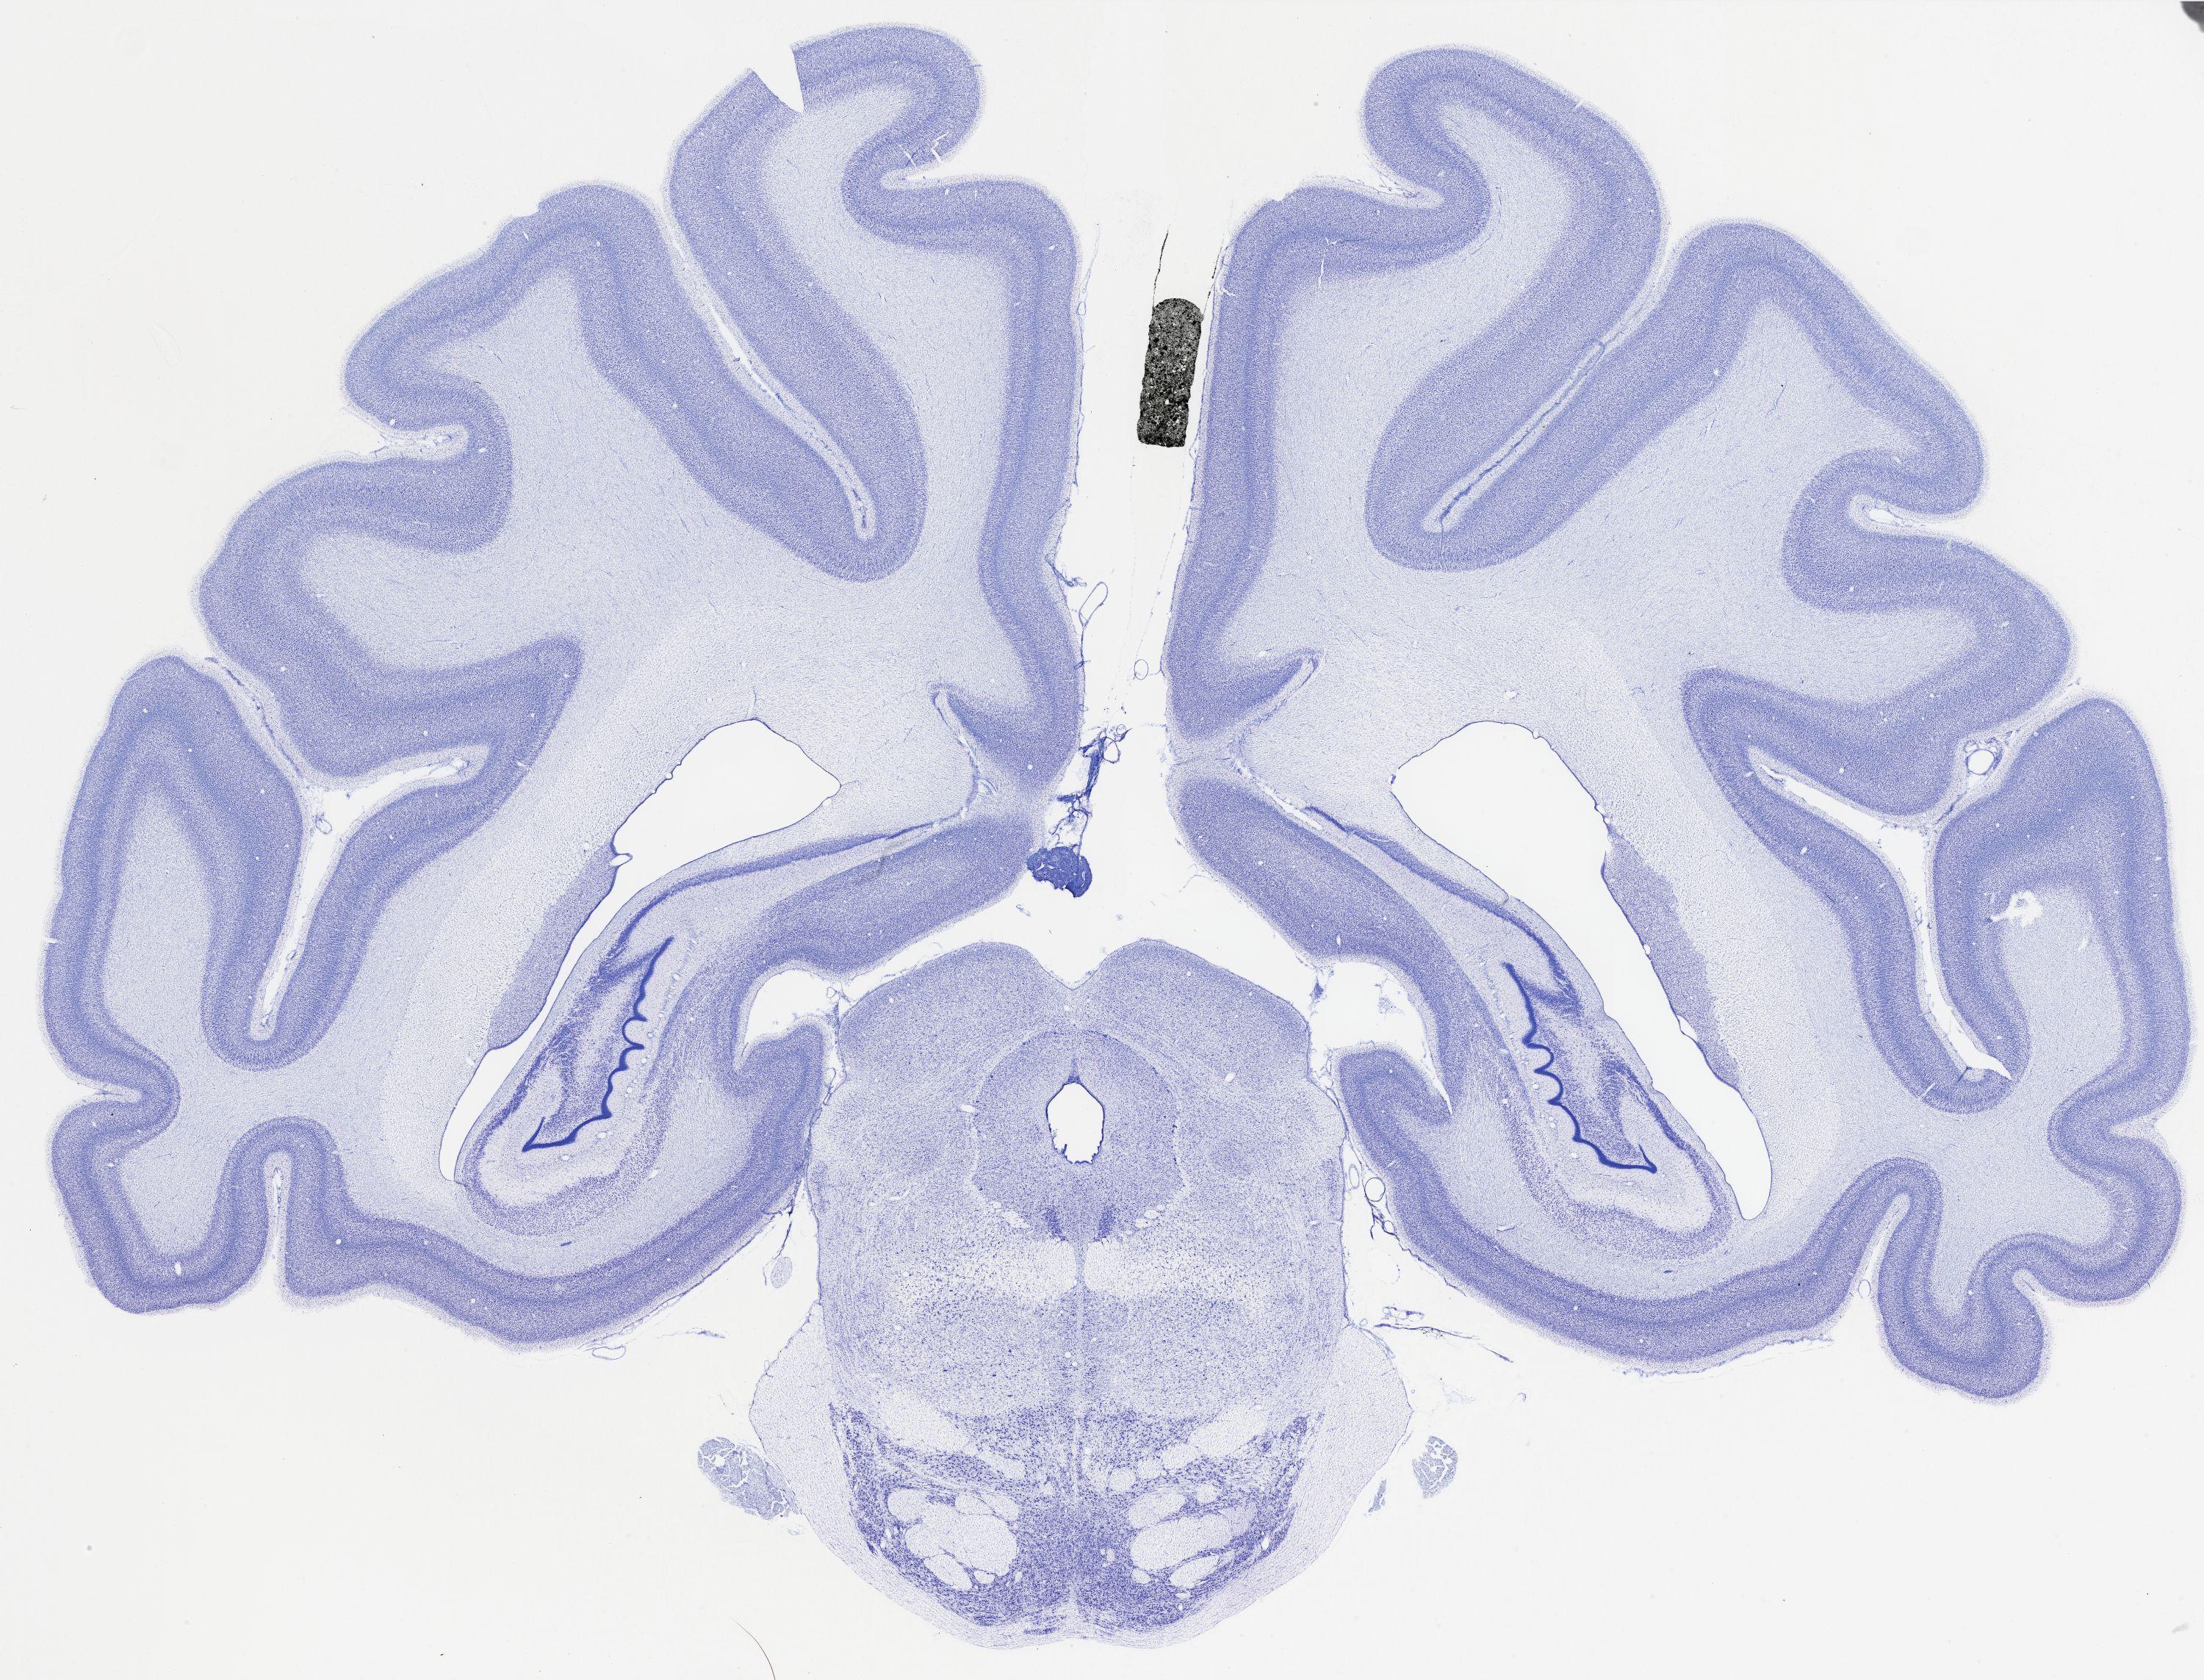

thumbnail

483